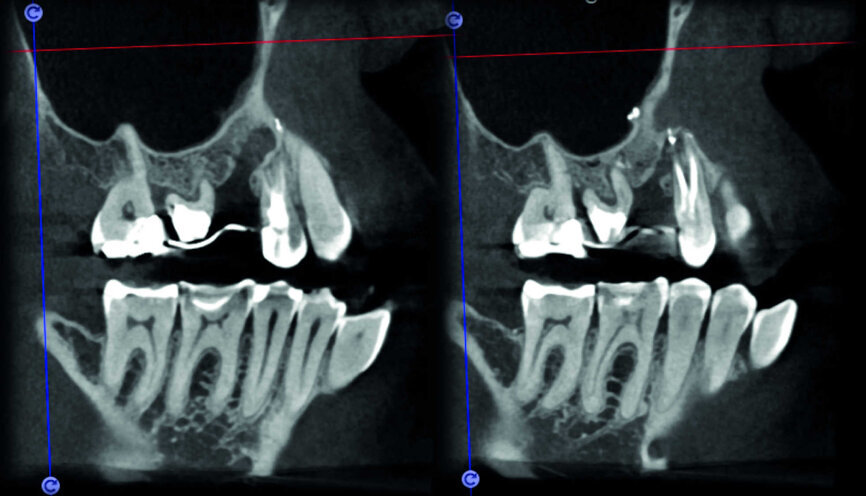

Le cas avec lequel je souhaite commencer mon exposé clinique est un exemple parfait de la difficulté à définir l’origine des symptômes d’un patient, par l’examen d’une simple radiographie intraorale. Non seulement l’examen 2D ne permet pas d’établir avec certitude la présence d’une lésion, mais surtout, il est impossible d’en déterminer la taille, la morphologie et le type. Au contraire, une analyse de l’imagerie 3D offre une image claire de la situation clinique. Chez ce patient, les coupes coronales et sagittales révèlent la présence d’une importante lésion s’étendant de l’apex de la racine mésiale de cette molaire jusqu’à la zone de furcation, tandis que les coupes axiales nous permettent d’analyser précisément l’anatomie endodontique et, en particulier, la forme de la racine mésiale, qui apparaît fusionnée avec la racine palatine. Un panorama complet du cas peut donc guider le processus de décision et orienter le plan de traitement vers une modalité bien précise de traitement (Figs. 1–4).

La comparaison des deux dents présentées dans les figures 10 à 22 démontre à quel point il importe d’analyser correctement toutes les coupes de l’examen CBCT. On peut voir que, dans la molaire maxillaire, la lésion commence sur la surface distale de la racine et pénètre dans la cavité pulpaire, mais s’arrête au tiers coronaire de la dent, sans affecter significativement l’intégrité du plancher de la cavité (Figs. 10–15). Les images cliniques illustrent les phases du traitement chirurgical, depuis le débridement de la résorption jusqu’à la restauration au moyen d’un ciment biocéramique (Figs. 16–19). Les clichés radiographiques finaux confirment le bien-fondé du traitement conservateur et endodontique de la dent. La situation est complètement différente pour la molaire mandibulaire, pour laquelle l’évaluation de l’examen CBCT révèle clairement l’étendue de la résorption, qui envahit le plancher de la cavité pulpaire jusqu’à la zone de furcation. Il serait impossible de détecter ce problème par le seul examen de la radiographie préopératoire (Figs. 20–22).